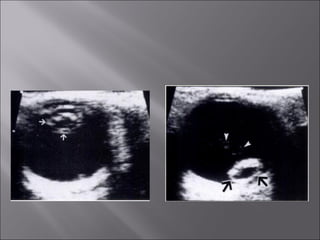

Ultrasound and CT scans provide anatomical images of the orbit, while color Doppler imaging provides visualizations of vascular structures and blood flow within lesions. These imaging techniques are used to evaluate a variety of orbital conditions involving blood vessels, infections, tumors, congenital issues, trauma, and more, and can help identify vascular disorders, thrombosis, treatment responses, and dynamic changes in benign tumors over time.